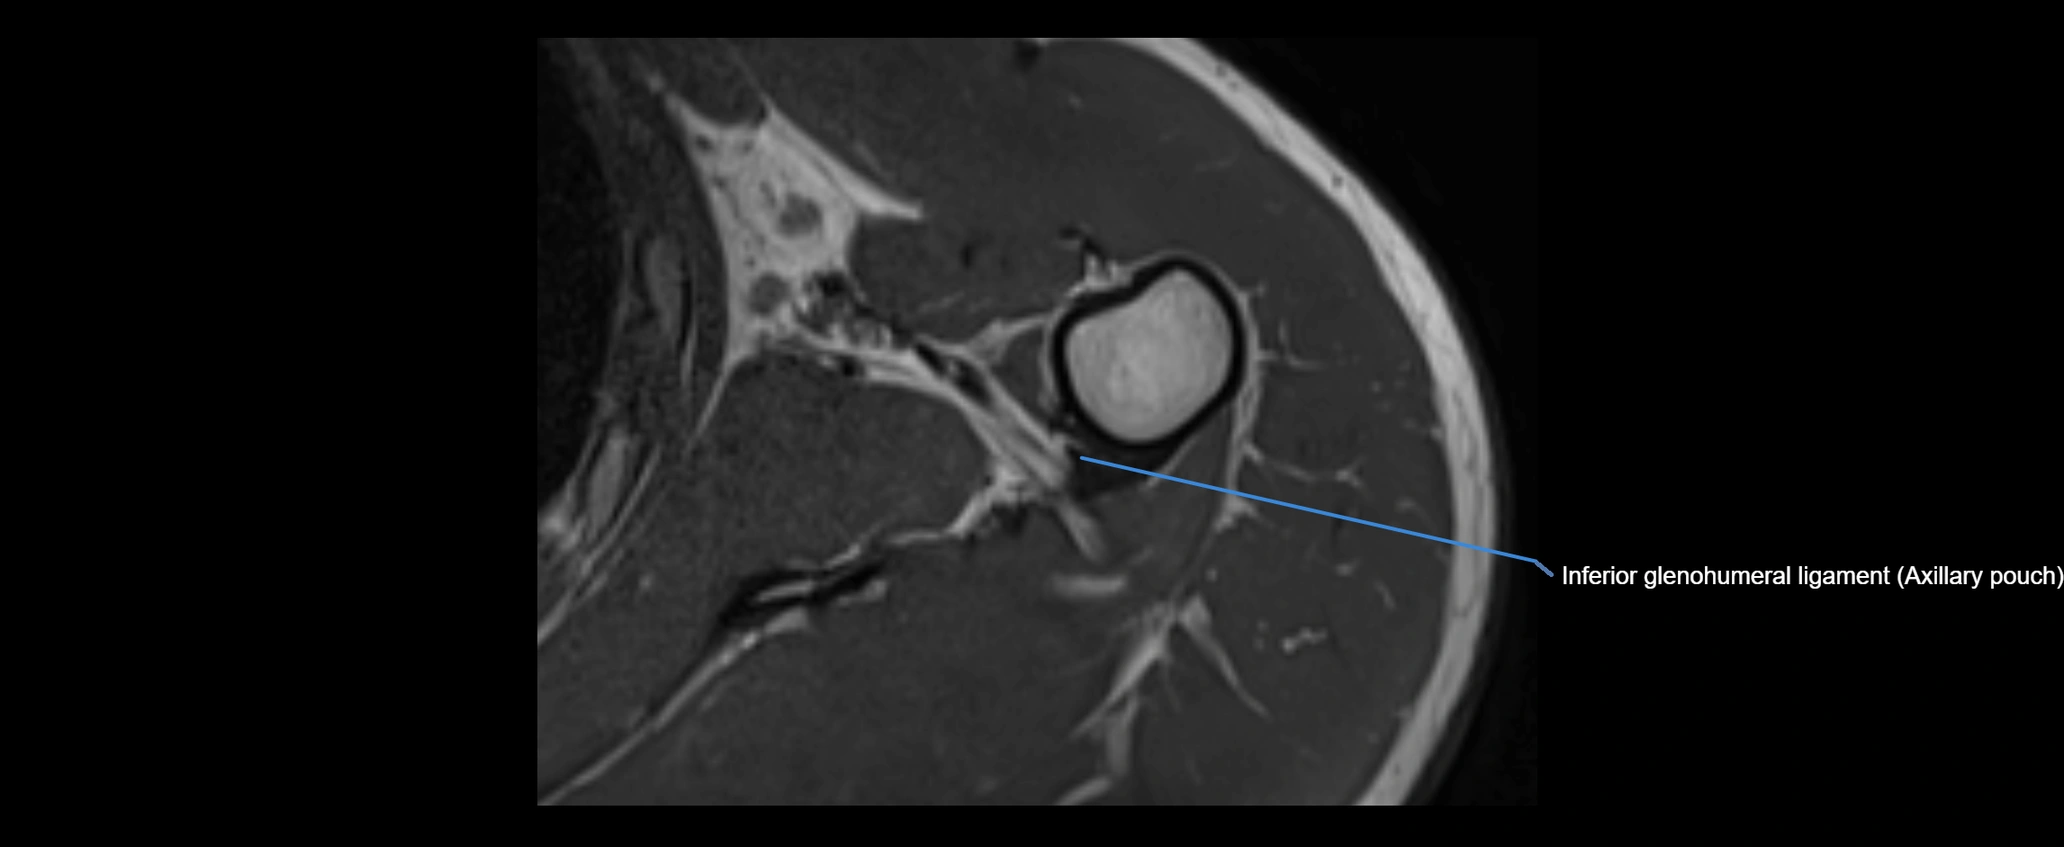

MRI images

image